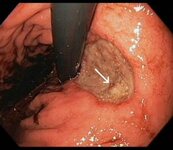

Large gastric ulcer along the lesser curvature with a visible vessel in the ulcer bed (arrow)

From the collection of Douglas G. Adler, MD